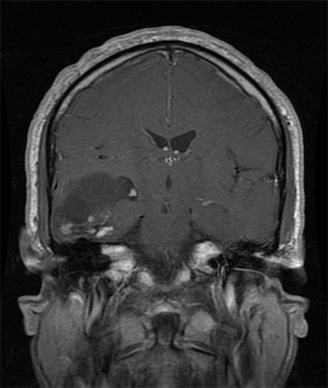

Oligodendroglioma: MRI T1 with gadolinium contrast, coronal section; source: RadsWiki, Wikimedia Commons